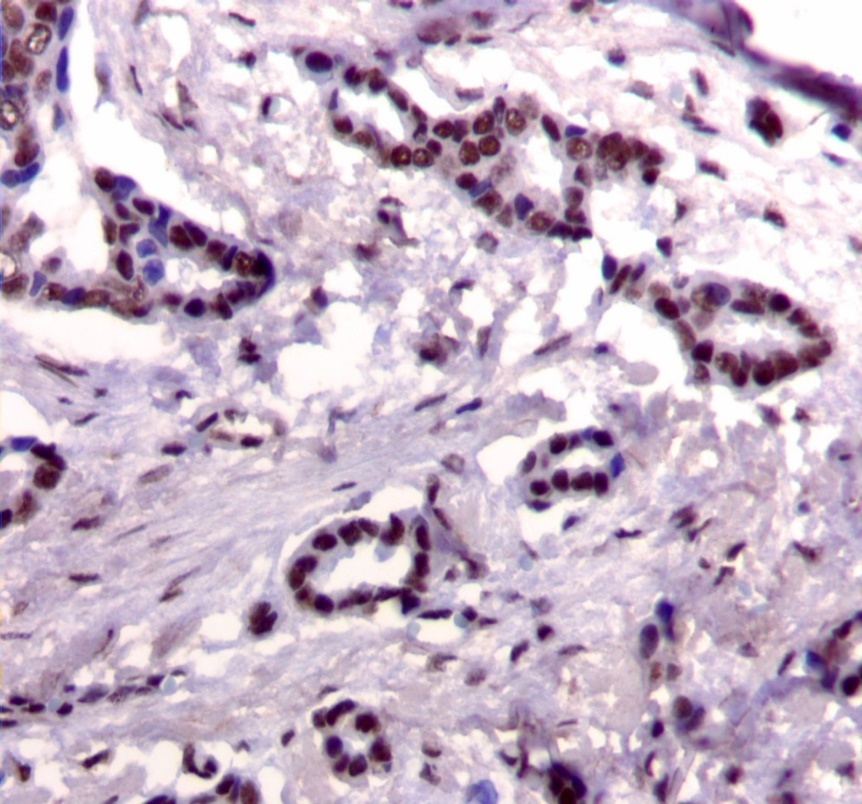

Figure 2.Diffuse cytoplasmic staining pattern for IRS-2. (IRS-2 immunohistochemical stain, 200x magnification)

Diffuse cytoplasmic staining pattern for IRS-2. (IRS-2 immunohistochemical stain, 200x magnification)

We used the following histologic criteria for IRS-1 and IRS-2 staining patterns which are outlined in a previous study.13 For IRS-1, a nuclear pattern was defined as diffuse nuclear staining (Figure 1). IRS-2 staining patterns were defined using the following criteria: Diffuse cytoplasmic staining was defined as evenly distributed cytoplasmic reactivity (Figure 2); punctate cytoplasmic staining was defined as clearly demarcated puncta of staining within the cytoplasm (Figure 3); and membrane staining was defined as focal or diffuse membranous staining (Figure 4). Sections of normal pancreas and normal breast tissue were used for positive and negative controls. The pathologists assessing staining patterns were blinded to the tumor recurrence score and all other data at the time of assessment.